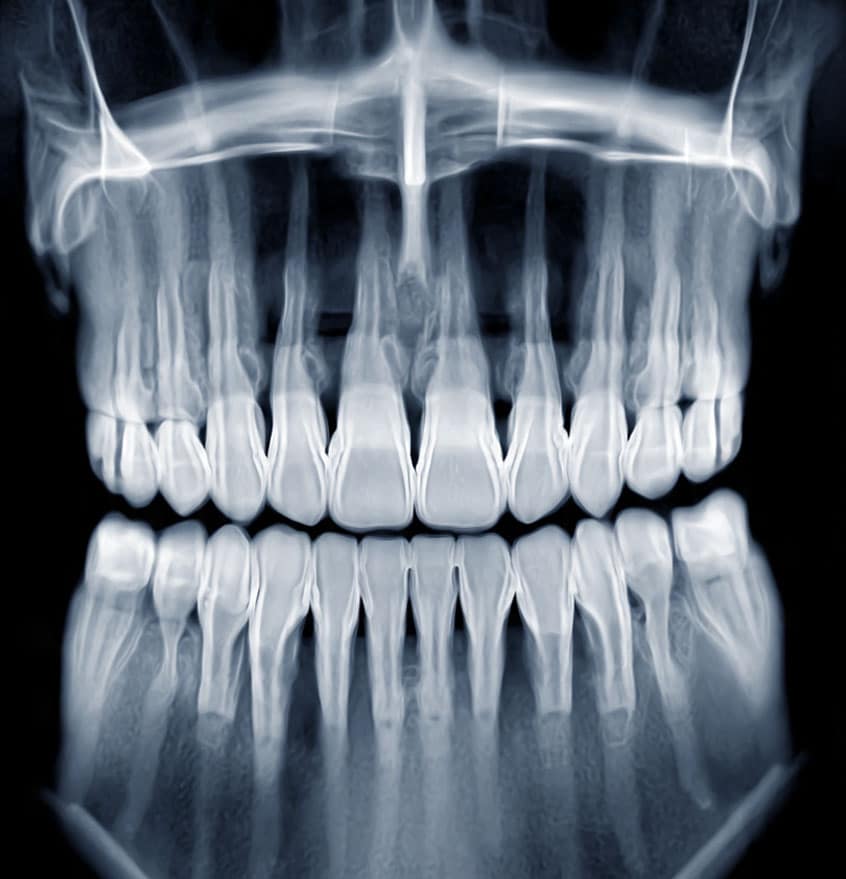

When you arrive, we take digital X-rays right away to find the source of the problem. Pain relief comes first — before any procedure begins. We explain exactly what we found and walk you through your options before anything is done.

• Digital X-ray to pinpoint the problem